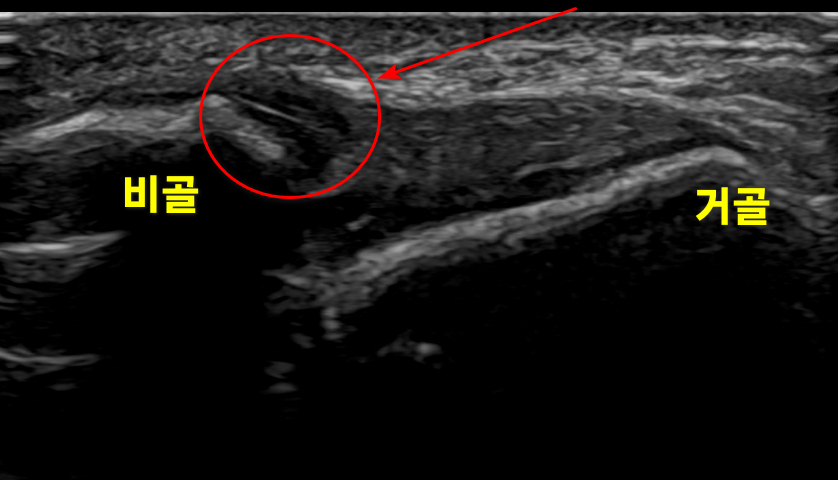

두번째 소개해드릴 환자분은

30대 남자분이셨는데요.

표준 초음파 영상과 달리

구불구불 곡선으로어둡게 부은 이 보이시죠?

환자 상태에 따라

침을 놓는 깊이가

달라지게 됩니다.

이런 만성 발목 염좌는

인대 부착부 골막 깊이까지자극해서 재생 치료를 하게 됩니다.